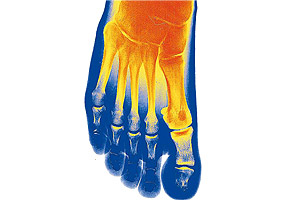

Bones of the foot

The foot is made up of three types of bones: tarsus, metatarsus and phalanges.

The tarsus is a cluster of bones that connect the leg to the metatarsus and is made up of the astragalus or talus (in the ankle), the calcaneus, the biggest bone of the foot making up the heel. Then there are five bones: the cuboids, scaphoids and the three cuneiforms.

There are five metatarsal or metatarsus bones in each foot and they extend from the tarsus to the toes or digits of the foot. Finally, we get to the phalanges, making up the toes, which conform 14 long bones in each foot. They are distributed into groups of three per toe, except for the big toe or hallux (where there are only two phalanges).